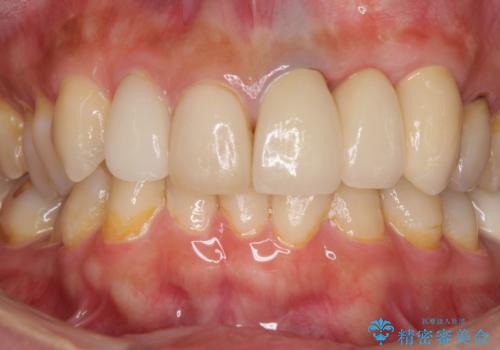

歯肉移植を用いた前歯のオールセラミックブリッジ

インプラントかブリッジか悩むところでしたが、既に治療されている前歯のクラウン周りの変色が気になっていたため、ブリッジにより色調を合わせたオールセラミックを装着することを選択しました。

歯肉ラインや歯の形態、色調を整えることができ、患者様には大変満足していただきました。